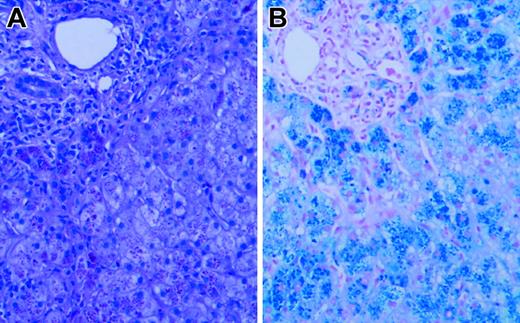

Liver biopsy revealed grade 4 hepatic parenchymal cell-stainable iron (Figure 1), portal and lobular inflammation (grade 3/4), and architectural distortion with portal-septal fibrosis (stage 3). Liver iron content by atomic absorption spectrophotometry was markedly elevated at 1500 μg iron/100 mg dry weight (normal, 1-17 μg iron/100 mg dry weight). Sequence analysis of HFE and HAMP revealed no mutations. Serum gonadotrophin analysis and intravenous glucose tolerance/insulin secretion test confirmed the presence of hypogonadotropic hypogonadism and diabetes, but endocrine function was otherwise normal.

Figure 1.

Liver biopsy. Hematoxylin and eosin (A) and Prussian blue iron (B) stains of the patient's liver biopsy specimen at the time of diagnosis, demonstrating heavy (4+) hepatocellular iron deposition. Slides were viewed with a Nikon Eclipse E600 microscope equipped with a 40×/0.75 objective lens (Nikon, Melville, NY). An RT Slider SPOT 2.3.1. camera and SPOT advanced software (v.3.5.9; Diagnostic Instruments, Sterling Heights, MI) were used to capture images.